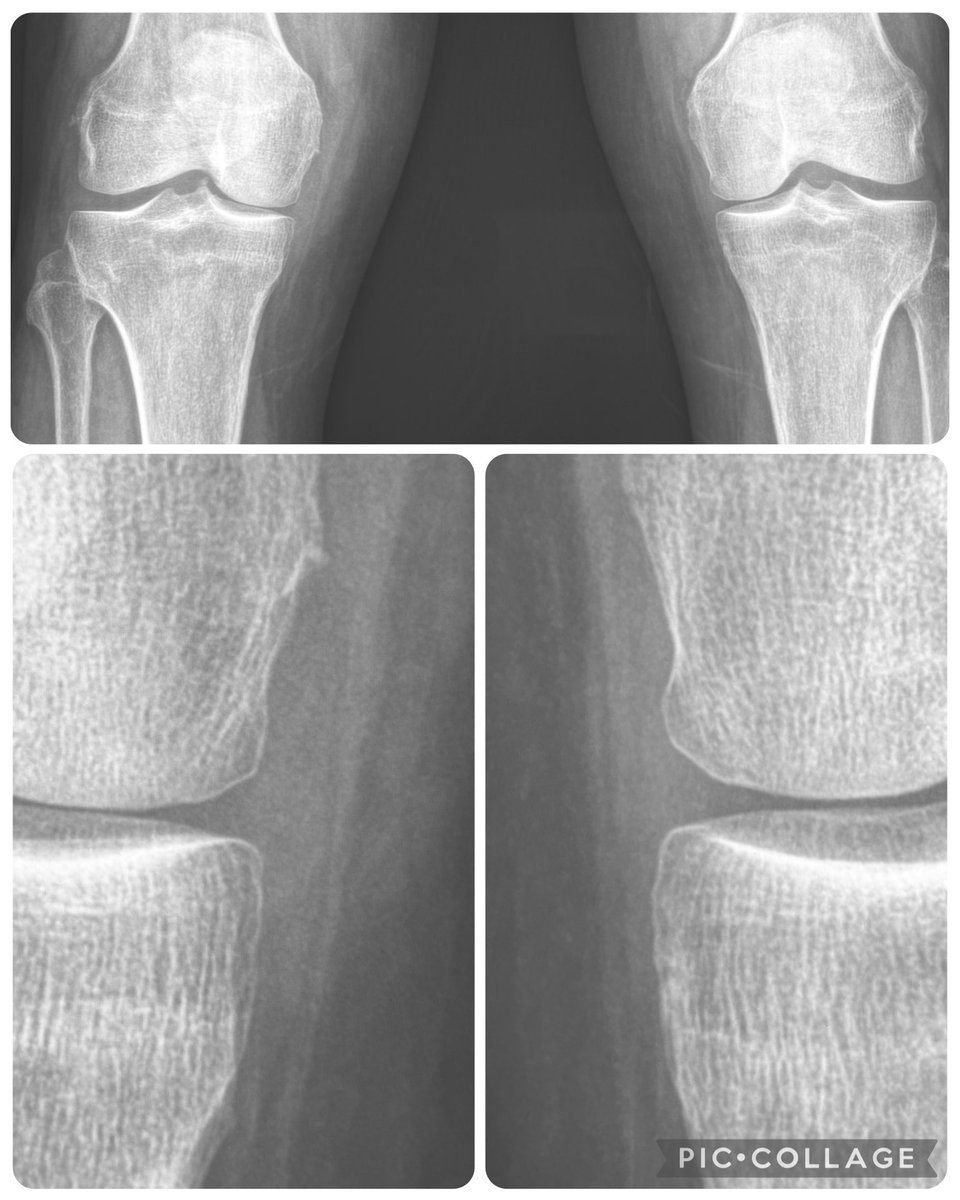

Before attributing ‘joint space narrowing’ at the knee to arthritis, take a look at the meniscus (yes, you can faintly see menisci on radiographs) - often the narrowing is due to meniscal extrusion, which in turn is related to meniscal tear.